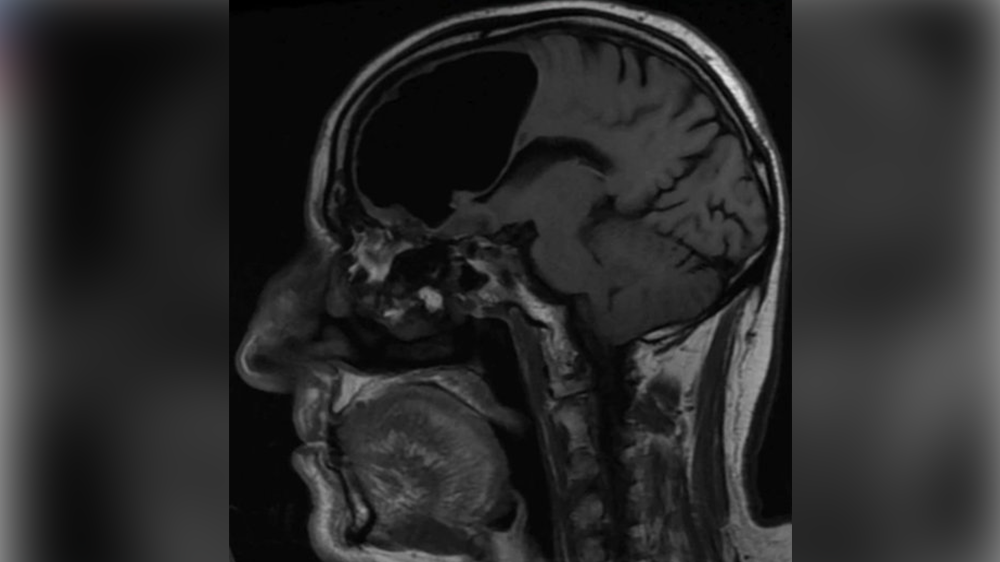

Increíble: Le hallaron hueco de aire donde debía estar su cerebro [FOTO]

Increíble: Le hallaron hueco de aire donde debía estar su cerebro [FOTO]